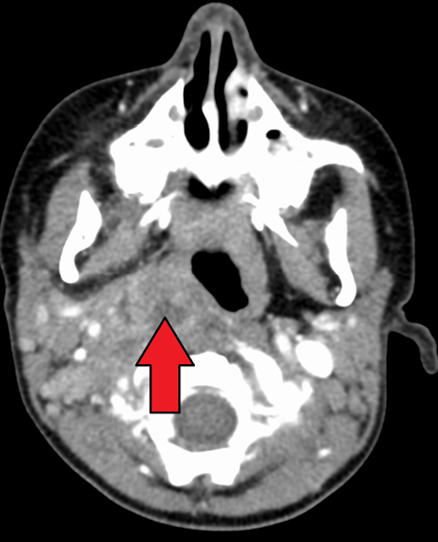

If there is concern for concomitant mediastinitis, an anterior-posterior and lateral chest X-ray should be obtained as well. CT imaging is the diagnostic modality of choice to identify deep-seated neck space abscess. (See Figure 5.) It can differentiate an abscess from cellulitis and can facilitate surgical planning with the otolaryngology team. Typically, the abscess will appear as a discrete fluid collection with surrounding rim enhancement.

Figure 5. Computed Tomography Scan of a Retropharyngeal Abscess |

Computed tomography scan demonstrating retropharyngeal abscess (red arrow). Courtesy of James Heilman, MD. LargeRetroAbsMarkTra. https://commons.wikimedia.org/wiki/File:LargeRetroAbsMarkTra.png CC BY-SA 4.0 |